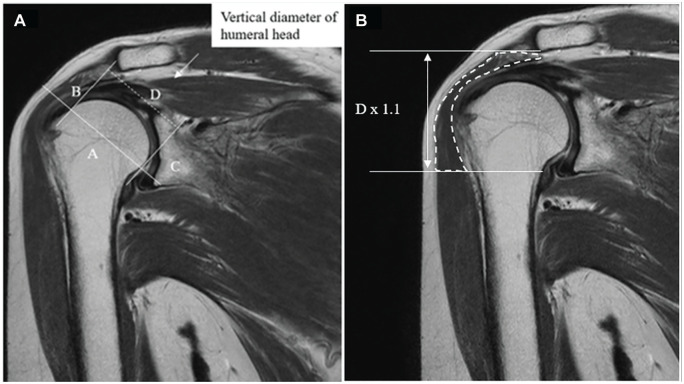

Methods: A total of 29 patients who underwent arthroscopic SCR using a fascia lata autograft were included. All received the same postoperative physical therapy. Active shoulder abduction and external rotation and American Shoulder and Elbow Surgeons (ASES) and Japanese Orthopaedic Association (JOA) scores were assessed preoperatively and 2 years postoperatively. Additionally, the acromiohumeral distance (AHD), rotator cuff tear size, and Goutallier/Fuchs and Hamada classifications were evaluated. Preoperative and postoperative deltoid muscle volumes were measured using a 3-dimensional reconstructed model from magnetic resonance imaging scans.